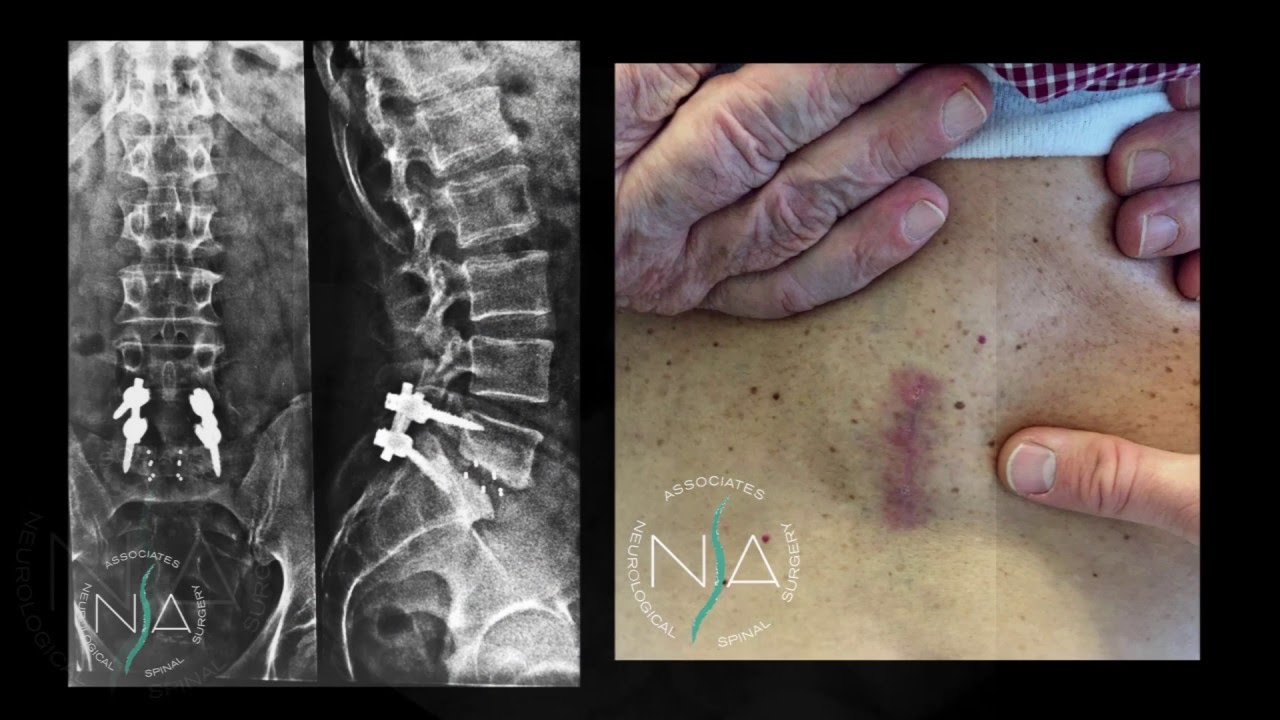

NEUROCHIRURGIA SPINALE :Trattamento di ernie discali, spondilosi e spondilodiscoartrosi attraverso Chirurgia endoscopica della colonna vertebrale, chirurgia laser assistita percutanea, epiduroscopia, chirurgia del dolore. Trattamento della instabilità vertebrale attraverso: stabilizzazioni spinali miniinvasive ed a cielo aperto del tratto lombare, dorsale e cervicale. Traumi spinali.

Foto e video